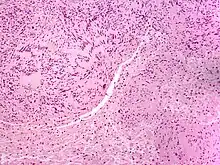

| Neuroma | |

| Solitary circumscribed neuroma | |

A neuroma (/njʊəˈroʊmə/; plural: neuromata or neuromas) is a growth or tumor of nerve tissue.[1] Neuromas tend to be benign (i.e. not cancerous); many nerve tumors, including those that are commonly malignant, are nowadays referred to by other terms.

Neuromas can arise from different types of nervous tissue, including the nerve fibers and their myelin sheath, as in the case of genuine neoplasms (growths) like ganglioneuromas and neurinomas.

The term is also used to refer to any swelling of a nerve, even in the absence of abnormal cell growth. In particular, traumatic neuroma results from trauma to a nerve, often during a surgical procedure. Morton's neuroma affects the foot. Neuromas can be painful, or sometimes, as in the case of acoustic neuromas, can give rise to other symptoms.